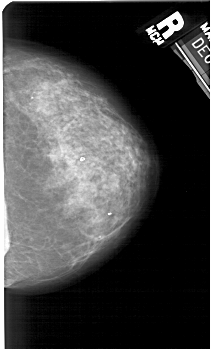

A_1362_1.RIGHT_CC

RIGHT_MLO LINES 5491 PIXELS_PER_LINE 3181 BITS_PER_PIXEL 12 RESOLUTION 43.5 NON_OVERLAY